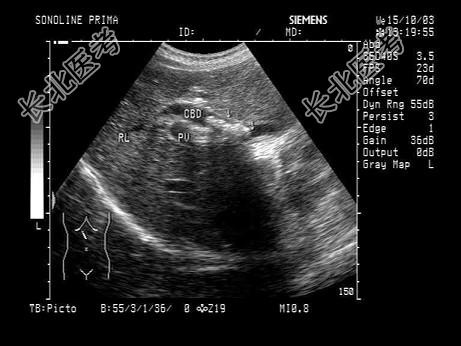

- 单项选择题女性患者,48岁, 上腹部剧烈疼痛2天。皮肤巩膜轻度黄染。声像图如图所示,诊断为 ( )

A、胆总管腺瘤

B、胆总管蛔虫

C、胆总管癌

D、胆总管胆汁淤积

E、胆总管结石